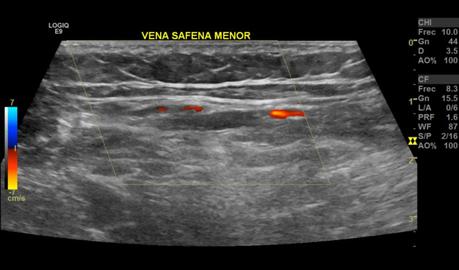

Se realizaron múltiples barridos ecográficos con transductor lineal de 9 MHz en escala de grises, Doppler color y espectral, con paciente en decúbito supino, efectuando valoración del sistema venoso superficial y profundo, observando siguientes hallazgos:

El sistema venoso superficial se observa con presencia de reflujo a la aplicación doppler a nivel de la vena safena mayor y vena safena menor.

• INSUFICIENCIA VENOSA SUPERFICIAL DE VENA SAFENA MAYOR Y VENA SAFENA MENOR, CON ALGUNAS VENAS ACCESORIAS EN TERCIO INFERIOR DE LA PIERNA.